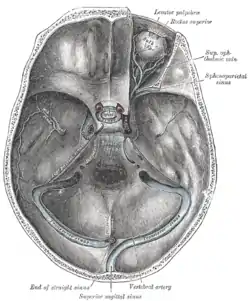

The basilar plexus (transverse or basilar sinus) consists of several interlacing venous channels between the layers of the dura mater over the basilar part of the occipital bone (the clivus) and serves to connect the two inferior petrosal sinuses.

It communicates with the anterior vertebral venous plexus.